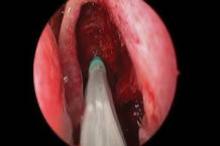

Photo courtesy Intersect ENT

The stent delivery system is shown advanced into the ethmoid cavity.